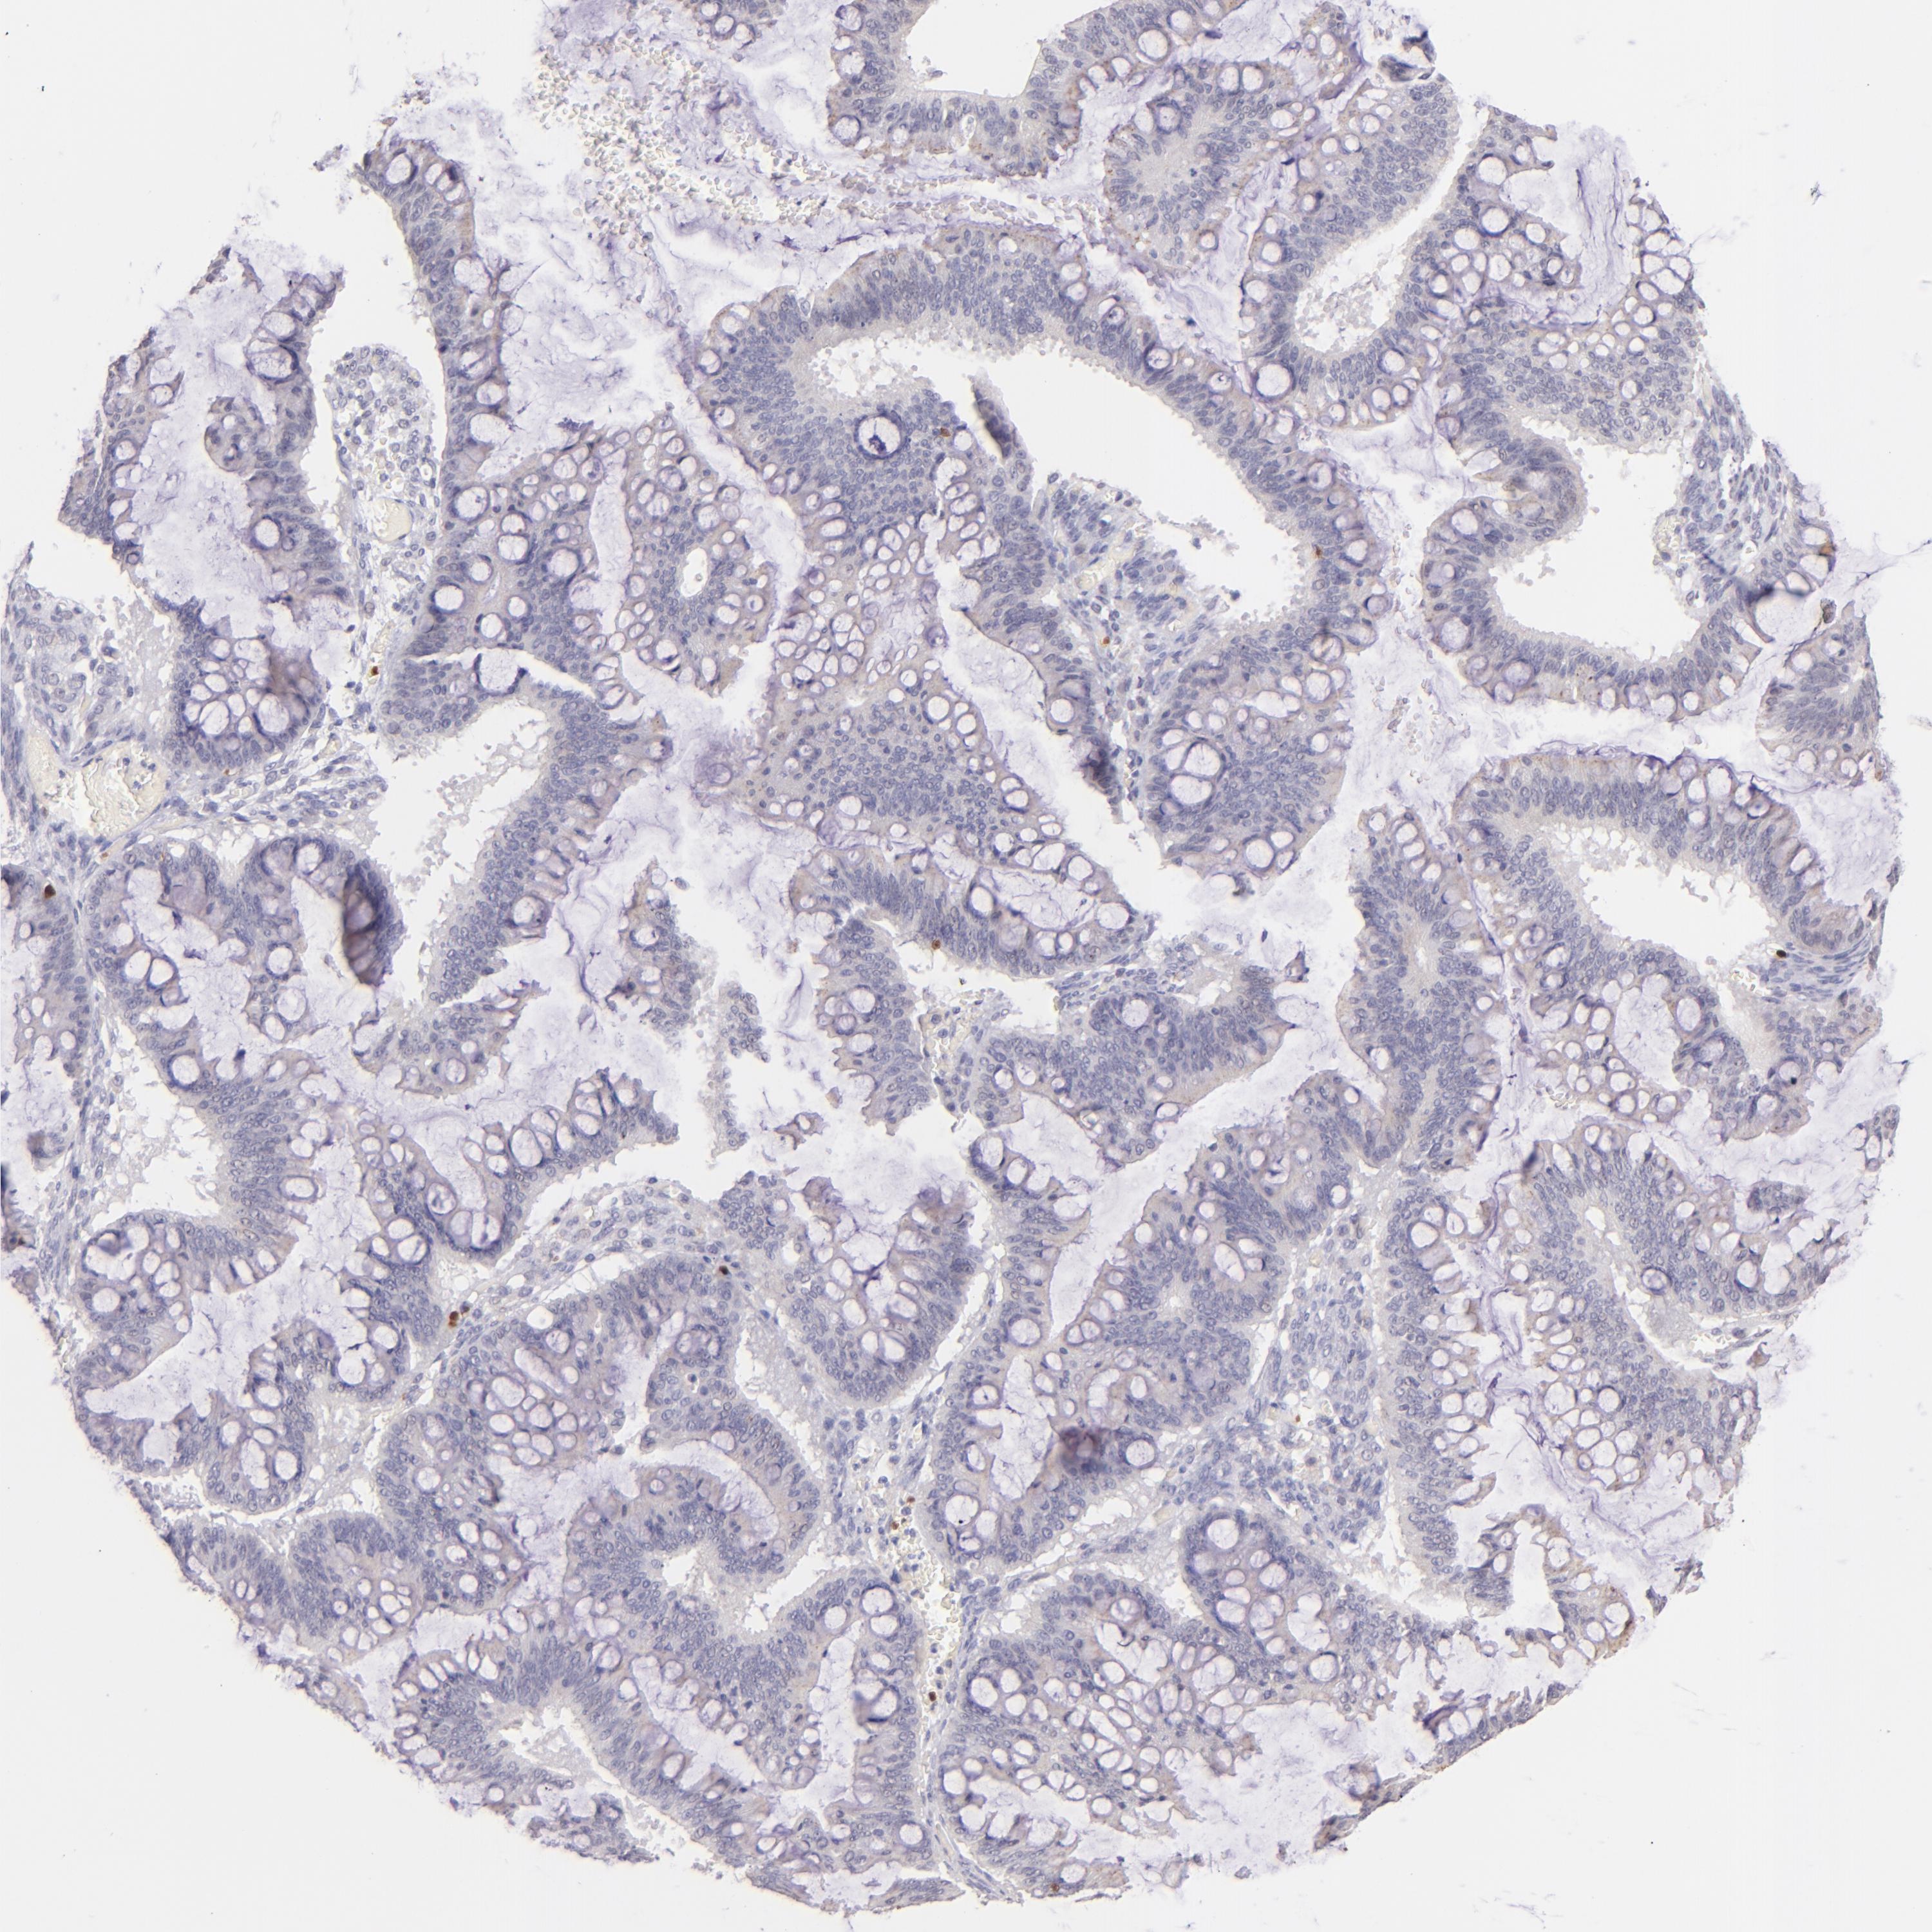

OVARIAN CANCER - Protein expressioni

A mouse-over function shows sample information and annotation data. Click on an image to view it in a full screen mode. Samples can be filtered based on level of antibody staining by selecting one or several of the following categories: high, medium, low and not detected. The assay and annotation is described here.

Note that samples used for immunohistochemistry by the Human Protein Atlas do not correspond to samples in the TCGA dataset.

Antibody stainingi

Antibody staining in the annotated cell types in the current human tissue is reported as not detected, low, medium, or high, based on conventional immunohistochemistry profiling in selected tissues. This score is based on the combination of the staining intensity and fraction of stained cells.

Each image is clickable and will lead to virtual microscopy that enables deeper exploration of all samples and also displays staining intensity scores, fraction scores and subcellular localization as well as patient and tissue information for each sample.

Antibody CAB002625

Cystadenocarcinoma, mucinous, NOS

Carcinoma, endometroid

Cystadenocarcinoma, serous, NOS